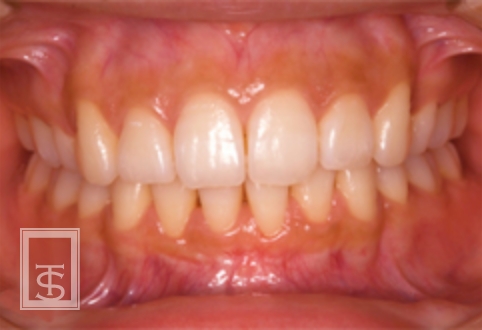

歯軸の重要性

歯軸とは、歯の長軸と上下顎基準平面との角度を意味しています。

審美的改善、機能的安定を獲得するには個人個人に合わせた歯軸の設定が必要です。

また、歯軸の設定は矯正治療時の抜歯判定の基準として用いられます。